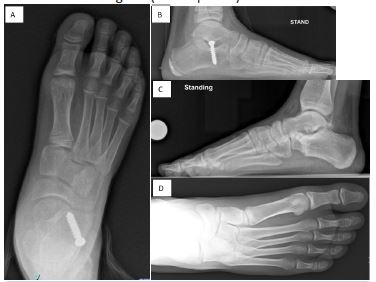

Radiographic evaluation of deformity correction included measurement of the calcaneal pitch angle (normal range, 18°–32°), Meary’s angle (normal range, –4° to +4°), and talonavicular coverage angle (normal, < 7°) [10,11]. Coalition was confirmed radiographically with CT (Figure 1). Hindfoot valgus was measured on coronal CT reformats, with a valgus angle greater than 16° considered the threshold beyond which isolated RC was not recommended [6,12,13].

Figure 1: CT scan conformation of talo-calcaneal coalition with hindfoot valgus.